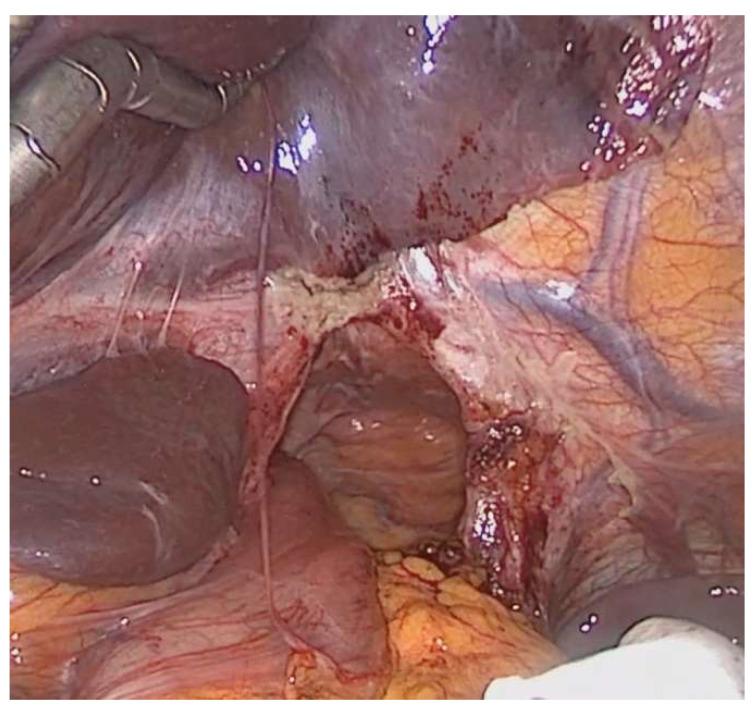

纳入306例患者(152例行HMIE;154例行OE)。其中,23例患者(8%)发生PHH。大多数患者(13/23,57%)在诊断时无症状,仅有4例患者(17%)因嵌顿而急诊就诊。与OE相比,HMIE后PHH的发生率显著更高(13.8%对1.3%,<0.001)。在单因素或多因素分析中未发现其他PHH发生的危险因素。19/23例患者(83%)接受了PHH的手术修复。手术修复后PHH的复发率为32%(6/19例患者)。

结论

PHH的发生是杂交微创食管切除术后的一种相关并发症。尽管大多数患者无症状,但建议进行手术修复以避免嵌顿导致潜在的致命后果。迫切需要预防和修复PHH的创新技术。